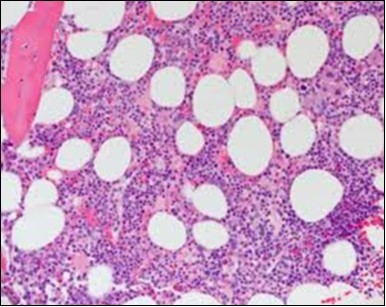

The classic hairy cell is medium sized with a magnitude of 10-14µm. The moderately abundant or variable cytoplasm may be transparent or mildly basophilic. The cellular surface with the characteristic serrated perimeter depicts innumerable fragile or stout extensions of cytoplasm ,particularly discernible on the phase contrast and electron microscopy. The cytoplasm may exhibit vacuoles with occasional azurophilic granules4. The nucleus may be elliptical or reniform, folded or indented with a coarse, reticulated or a finely dispersed chromatin and inconspicuous nucleoli along with infrequent mitosis. Bone marrow aspiration or bone marrow trephine biopsy may be inadequate for diagnosis in 30%-50% individuals4. The trephine sections of the bone marrow may depict a characteristic interstitial pattern of leukaemic infiltration. Generally the bone marrow is hyper-cellular, though it may be hypo-cellular in 10-15% individuals4. The leukaemia cell ingress may be diffuse or partial, although diffuse infiltration is frequent. The partial variety of leukaemic dissemination may be ineptly categorized with an indeterminate differentiation from the uninvolved marrow. The malignant insertions may initially emerge as miniature, undefined, cellular loci. The formalin fixed, paraffin embedded sections may elucidate a crystalline zone or a “halo” appearance of the cells with a circumscribed nucleus on account of the plentiful cytoplasm4. The cellular margins may be intertwined. Fixation of bone marrow smears with Zenker’s fixative may demonstrate a retracted cytoplasm of the hairy cells with a consequent disconnected structure. The bone marrow in the absence of a malignant process may be hypo-cellular or hyper-cellular. Reticulin stains may delineate an enhanced accrual of broad, dense reticulum fibres surrounding the aggregates of leukaemia cells with the fibrous circumlocution of individual malignant cell and fibrotic extensions into the abutting, uninvolved bone marrow4.

The leukaemia cells may enunciate a characteristic immune phenotype, crucial for a confirmatory diagnosis. The peripheral blood mononuclear B cell population may display a kappa or lambda light chain restriction. The phenotype of classic hairy cell leukaemia may be delineated by concurrent, immune reactive CD19+ CD20+,CD 11c+, CD25+, CD103+ and CD123+. An intensely immune reactive CD200+ and a non reactive CD27- antigen may be present2, 4. Evaluation of a trephine bone marrow biopsy and bone marrow aspirate may define the degree of tumour infiltration. A dry tap on account of prominent bone marrow fibrosis may be elucidated at preliminary diagnosis. A decline in the normal haematopoiesis may account for a hypo-cellular marrow in 10% instances. Gradation of cellular infiltrating of the leukaemia within the bone marrow may be appropriately investigated with immune –histochemical stains2, 4. Immune staining for CD20+, annexin 1 and VE1 (a BRAF V600E stain] may validate the diagnosis and precisely analyse the extent of malignant bone marrow infiltration[8]. Determination of BRAF V600E mutation may be critical in therapeutically non responsive individuals with applicable standard therapy or in instances of multitudinous reoccurrences[9]. Deploying inhibitors of BRAF V600E gene may be efficacious in patients impervious to approved therapy. The mutation necessitates a comprehensive scrutiny of the implicated individuals with a sensitive molecular assay which may discern up to < 10% of the hairy leukaemia cells appearing in the peripheral blood smears or bone marrow aspirates diluted with peripheral blood or aspirates elucidating a dry tap[2,4]. Allele specific polymerase chain reaction (PCR) or a next generation sequencing may be optimally employed to circumvent false negative outcomes. If the leukaemia cells are sparse or if particularly sensitive & efficacious molecular techniques are not accessible, the application of appropriate immune histochemical stains to the bone marrow biopsy such as a BRAF V600E mutation stain (VE1) may detect the hairy cells and conclusively diagnose the condition[2,4,10]. Figure 1, Figure 2, Figure 3, Figure 4, Figure 5, Figure 6, Figure 7, Figure 8, Figure 9, Figure 10, Figure 11, Figure 12, Figure 13, Figure 14.

Figure 1.HCL: hairy cells infiltrating designated spaces(17).

Figure 2.HCL: hairy cells with projecting cytoplasm abutting bony trabaculae(18).

Figure 3.HCL: hairy cells dispersed within the native architecture(19).

Figure 4.HCL: hairy cells with widely spaced nuclei(20).